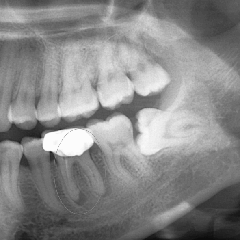

牙齒矯正前拍全景片